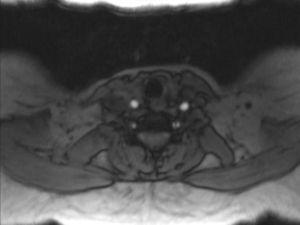

In order to find out the cause for her worsening headache MRI-Brain with MR-Angiography (MRA) was performed which revealed subarachnoid hemorrhage over bilateral parietal, occipital and in perimesencephalic cistern with severe vasospasm of bilateral posterior cerebral, middle cerebral and anterior cerebral arteries. She was then subjected to digital subtraction angiography which showed narrowed V2 segment of left vertebral artery, small dissecting aneurysm of V3 segment of left vertebral artery, severe narrowing of distal V2 segment of right vertebral artery and mild focal narrowing of intradural right vertebral artery suggesting bilateral multiple vertebral artery dissection. There was no intracranial aneurysm or arterio-venous malformations and venous system was normal. MRA of neck vessels confirmed dissection of bilateral vertebral arteries at multiple levels (Figs. 1 and 2). Vasculitis work-up was done to find out the cause for VAD, which came negative for ANA, dsDNA, c-ANCA, p-ANCA, anti-cardiolipin antibody, anti-phospholipid antibody and VDRL. As there was no history of trauma, a diagnosis of spontaneous VAD was made.